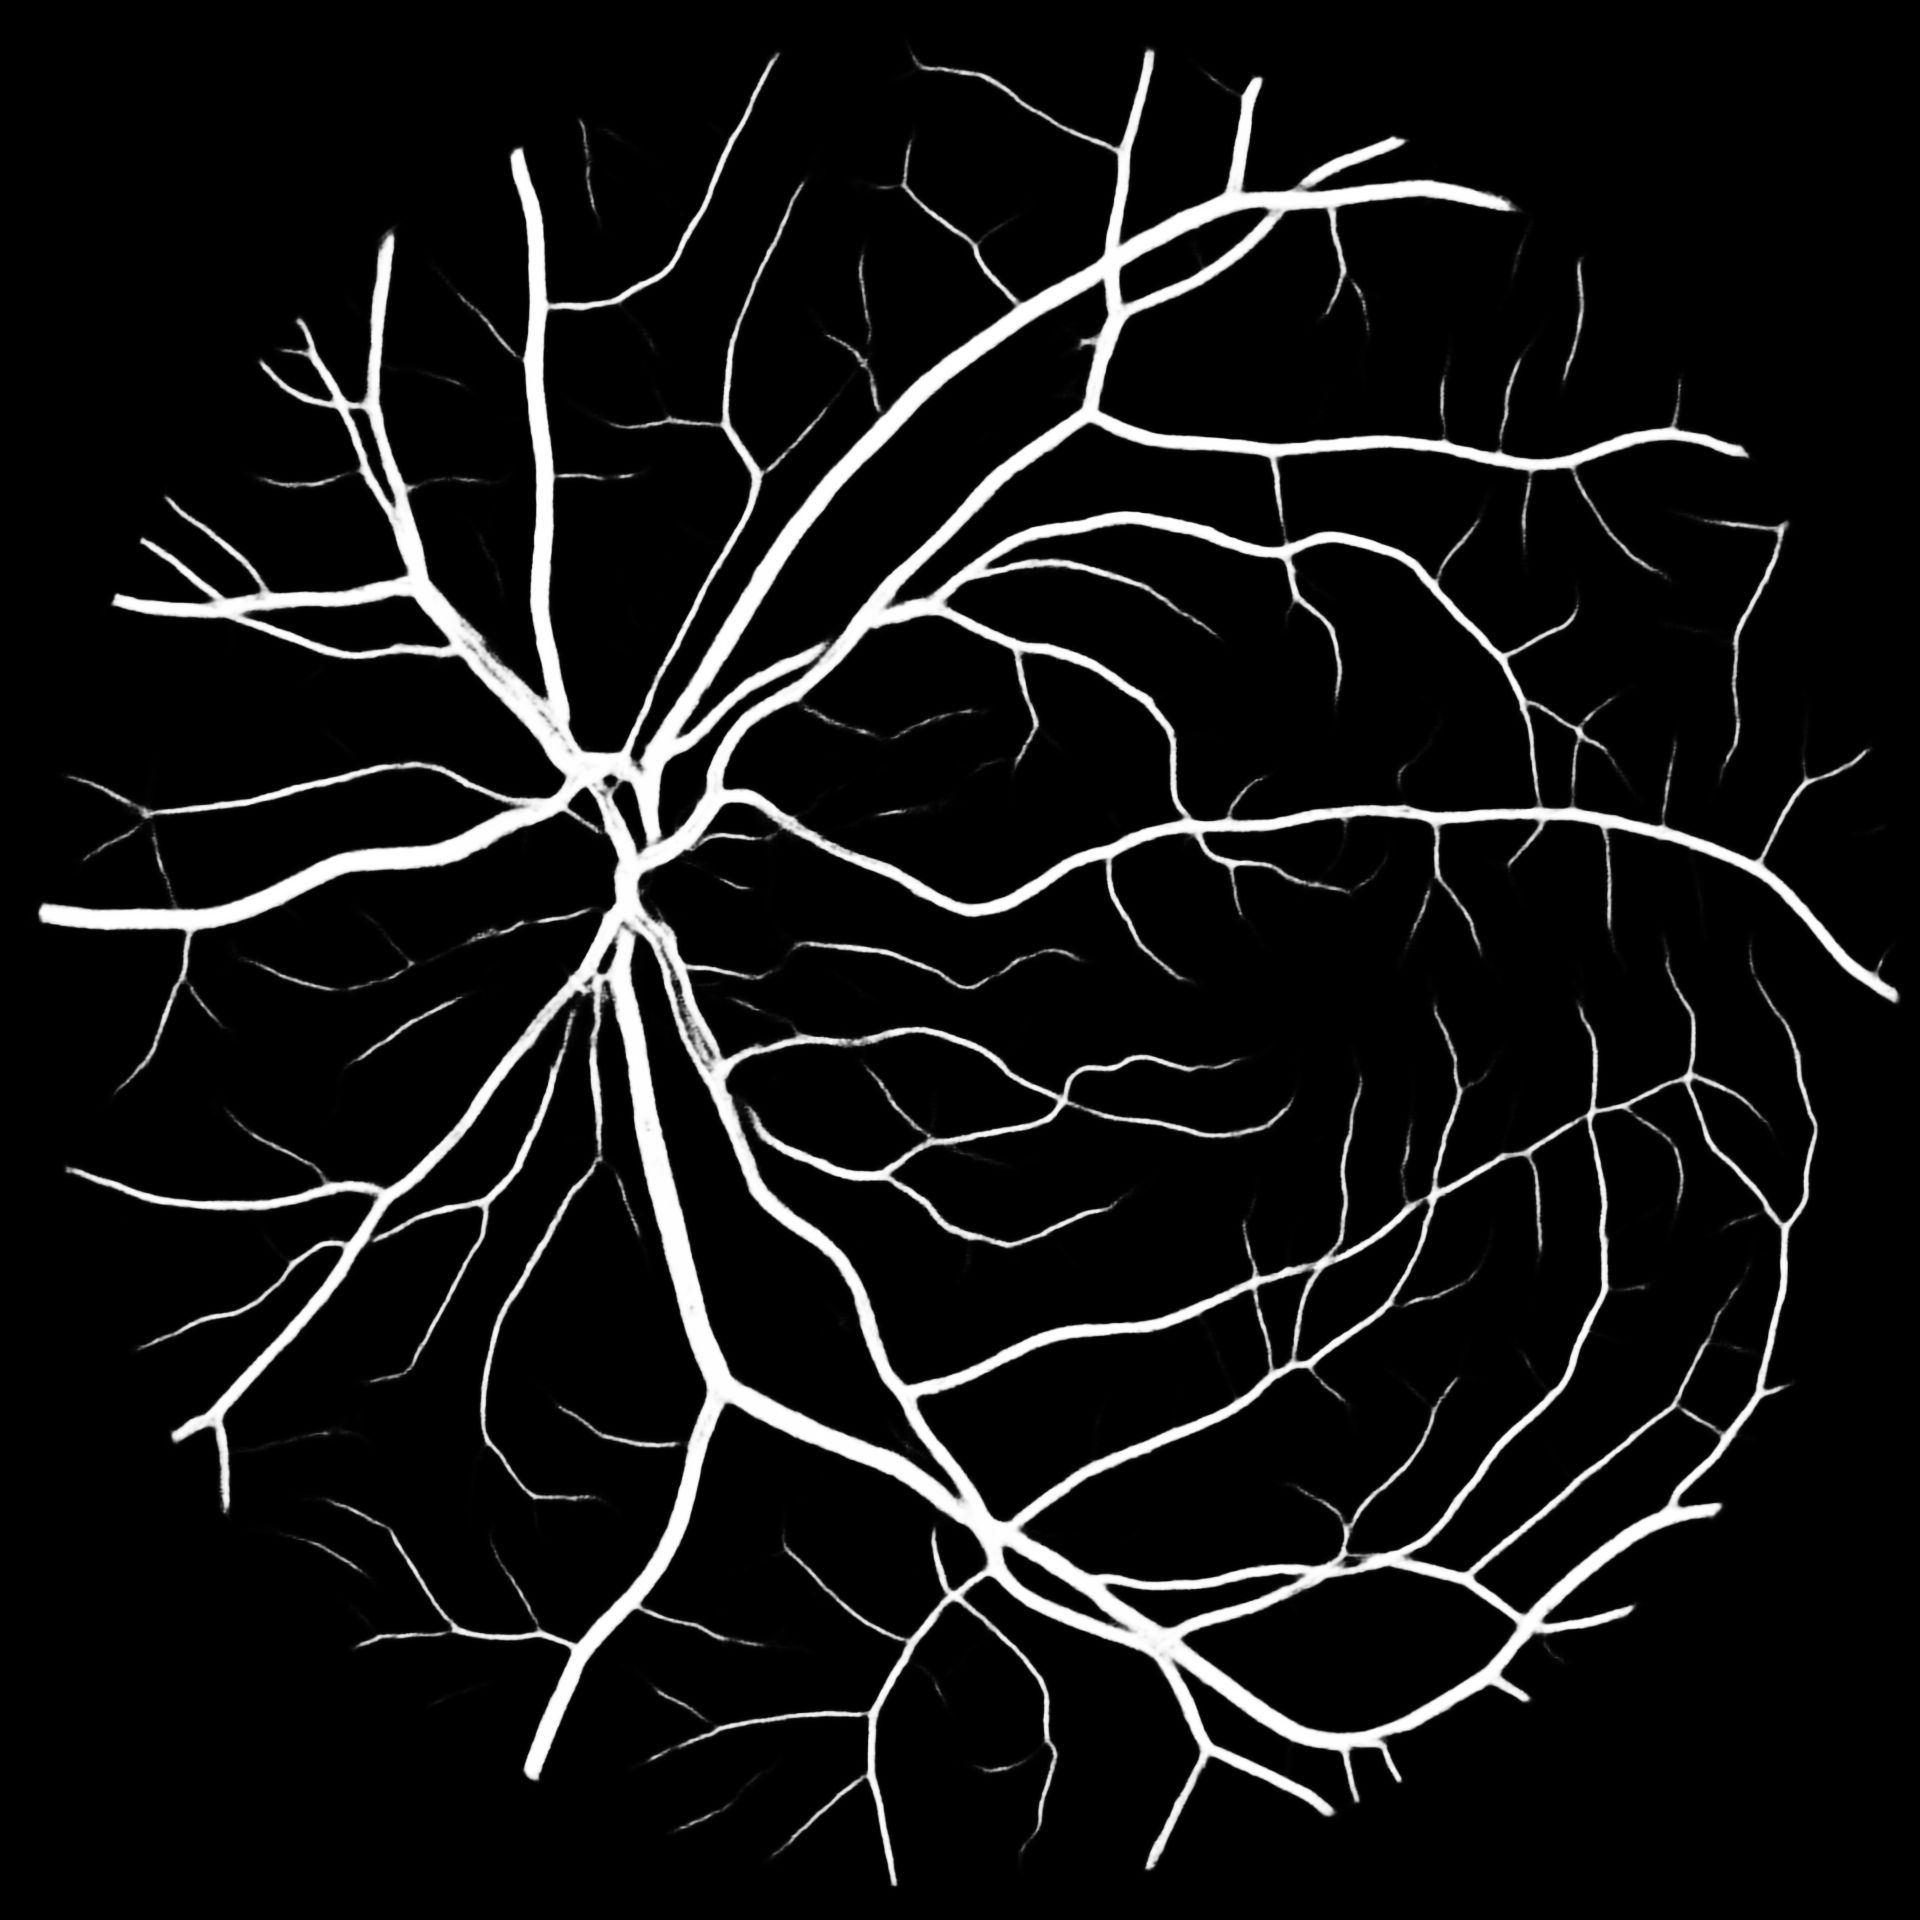

VI Evaluation

To put our results into perspective, Table V compares previous works to our methods. We report the -score for our results together with their standard deviation. Overall M2U-Net and DRIU trained on COVD are competitive, with the best performance on the high-resolution dataset HRF, where a new state-of-the-art F1-score could be reached. Additional metrics such as accuracy, sensitivity, precision and specificity are available in the documentation of our software package. Further, to the available public datasets, we trained M2U-Net on COVD for a private target dataset with a resolution of 1920x1920 for which no ground-truth data is available. The predicted vessel probability maps are displayed in Figure 5. While we can only make subjective statements, we find that the generated probability maps are of good quality, with the majority of main vessels being detected, even in presence of pathologies. An illustration of predicted vessel maps versus ground truths for M2U-Net on HRF is provided in Figure 4.

HRF

COVD

COVD– SSL